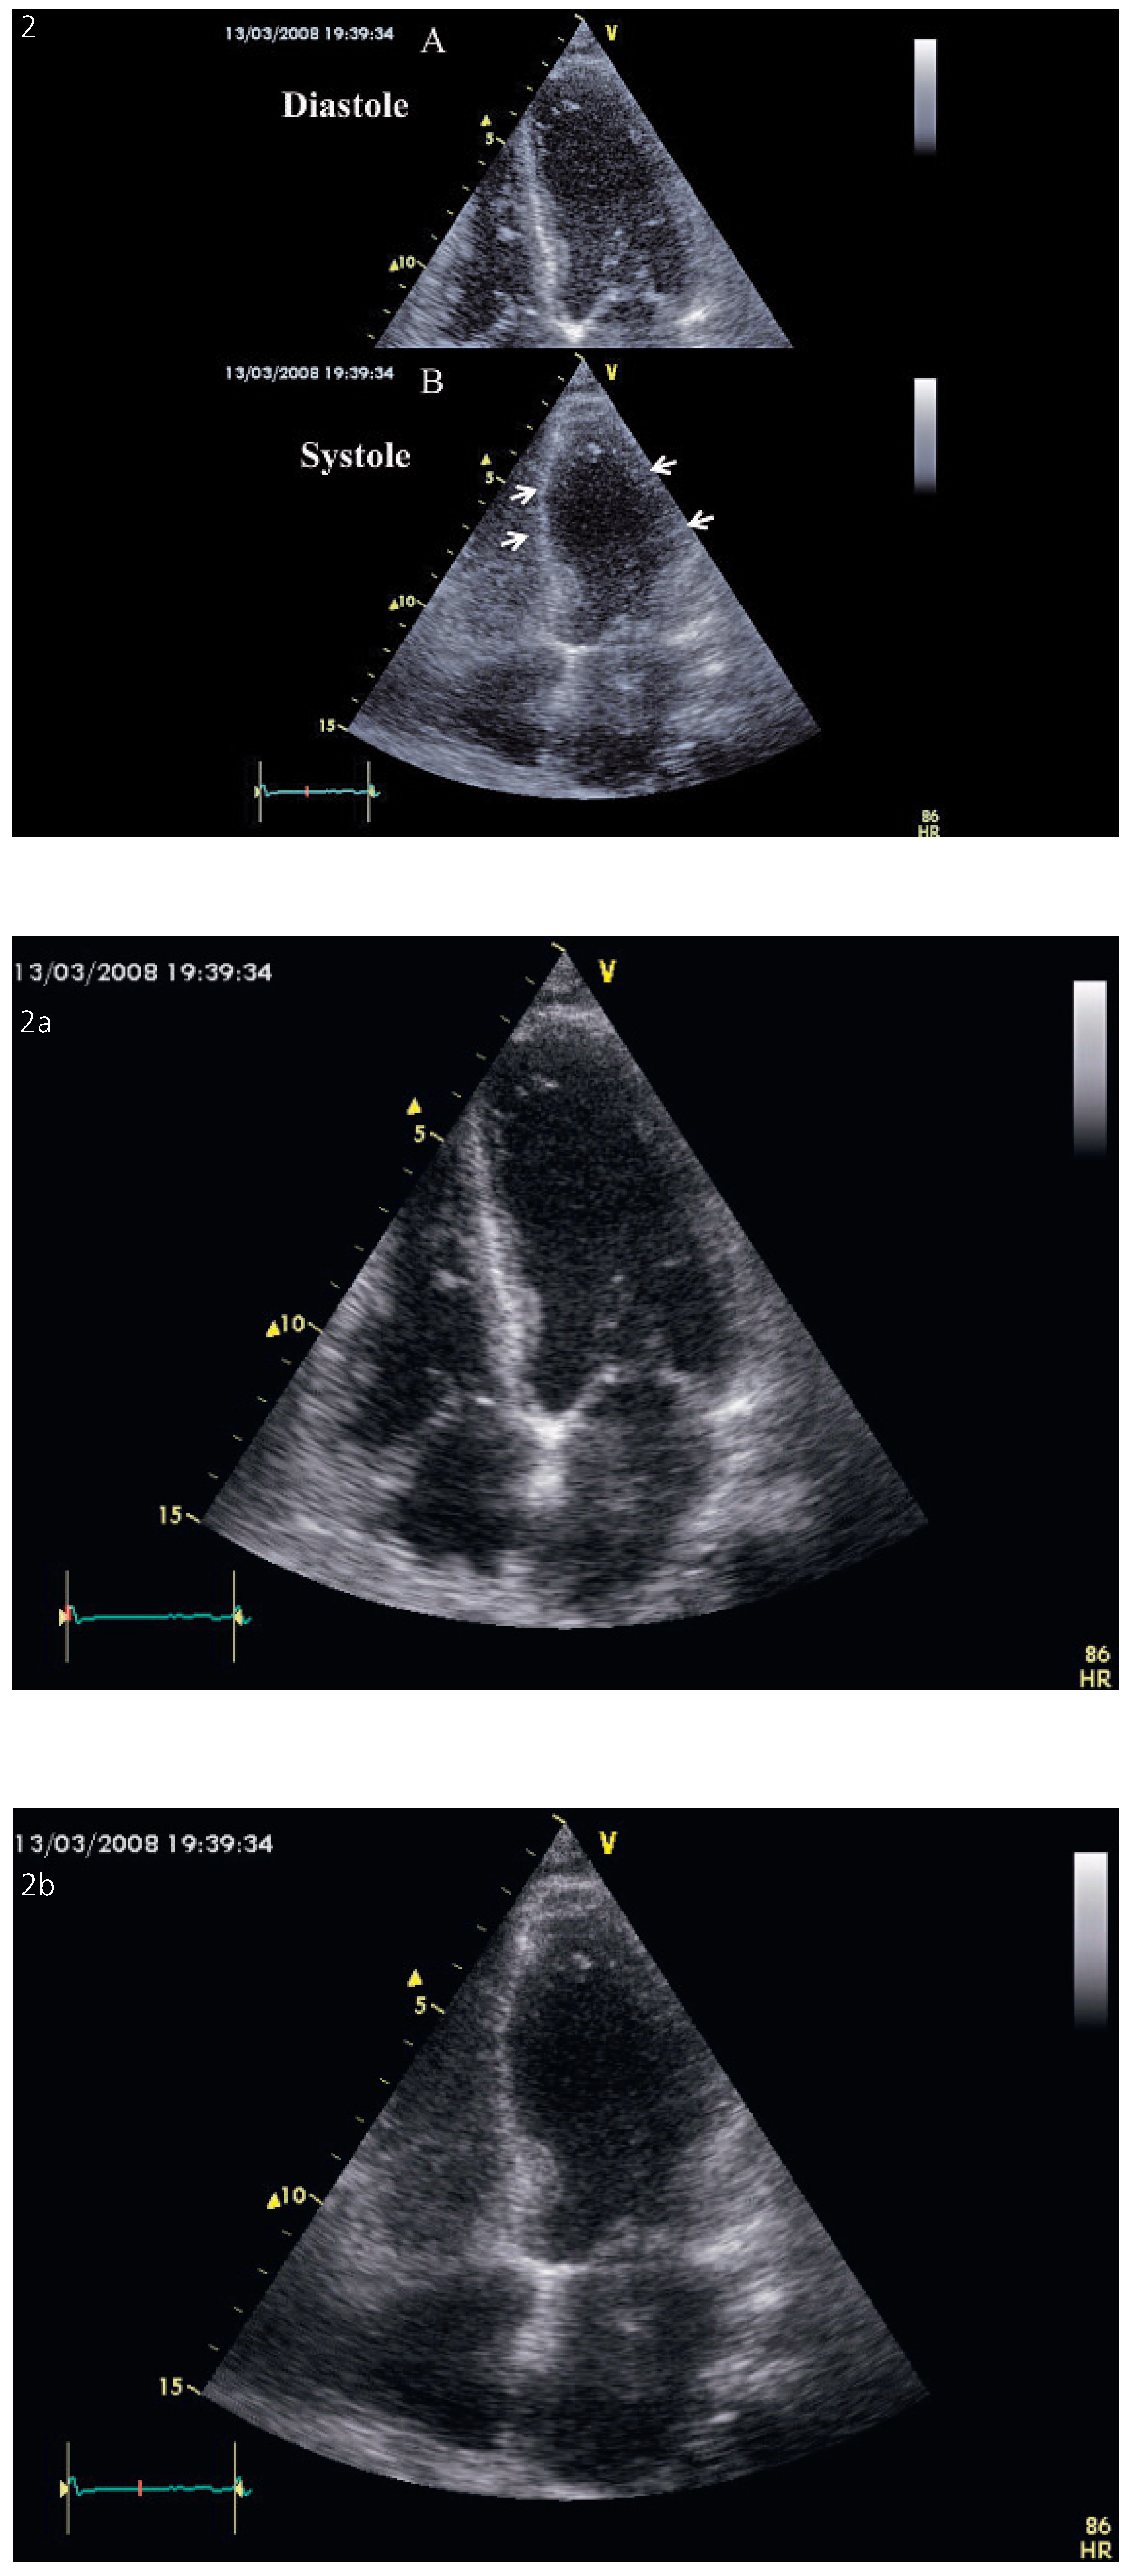

The majority of the patients presented a moderate to severe LV systolic dysfunction at the first echocardiogram with a mean LVEF of 37 ± 10% with a range of 15 to 55%. The dysfunction was secondary to an apical LV akinesis with an apical ballooning and a compensatory hypercontraction of the base in the typical forms of TC (90% of cases). In the four patients with cardiogenic shock, only a small annular basal ring was contracting and one patient exhibited a severe left ventricular outflow tract obstruction. Right ventricular involvement was present in 32% of cases. It was associated with a significantly lower left ventricular ejection fraction (31% vs 40%, p = 0.01). Atypical forms included isolated mid-ventricular akinesia in three patients (fig. 2). All the patients completely recovered their cardiac function in one week to three months. None of our patients exhibited the features of an asymmetrical hypertrophic cardiomyopathy.

Figure 2. (A.) Diastolic frame in a 4 chamber view showing a normal shape and appearance of the left ventricle. (B). In systole, there is a complete akinesia of the middle portion of the ventricle characteristic of mid ventricular form of Takotsubo cardiomyopathy (arrows).